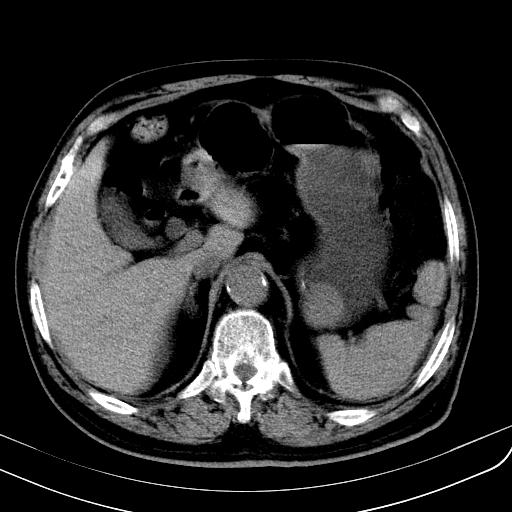

胃底靠近胃大弯处可见一圆形软组织影,直径为3.45cm,ct值约为30.1hu

边缘光滑,密度均匀,良性占位,首先考虑平滑肌瘤。

边缘光滑,密度均匀,良性占位,首先考虑平滑肌瘤。其实平滑肌瘤也是间质瘤的一种